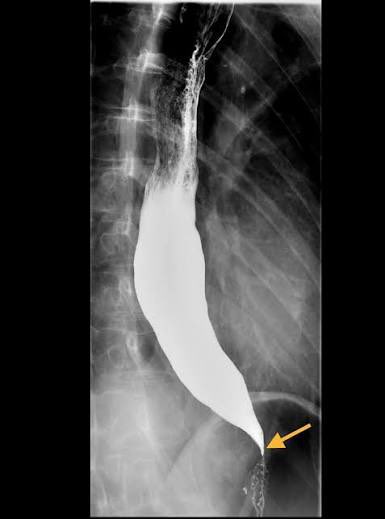

@md1talk Bird peak sign

Achalsia

EGD, Barium swallow, Chest CT scan with intravenous contrast to evaluate for pseudoachalasia